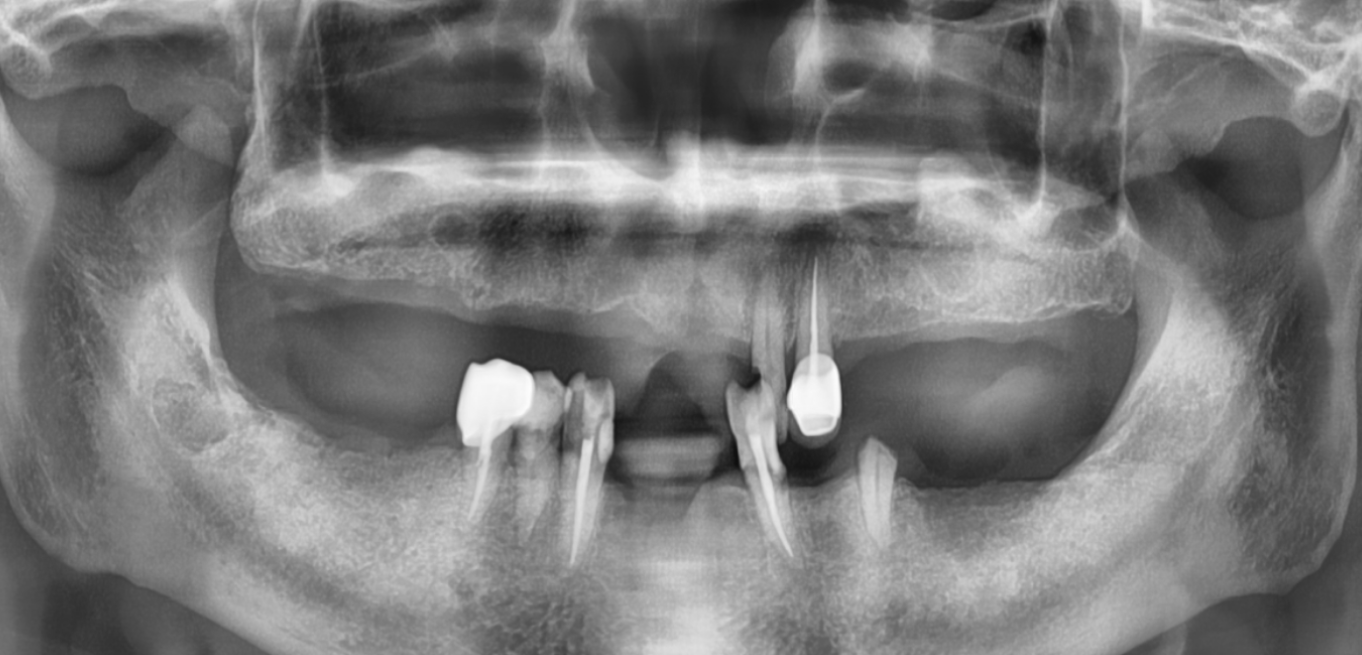

Before & After

Drag Before After

버튼을 움직여서 변화를 확인해보세요.